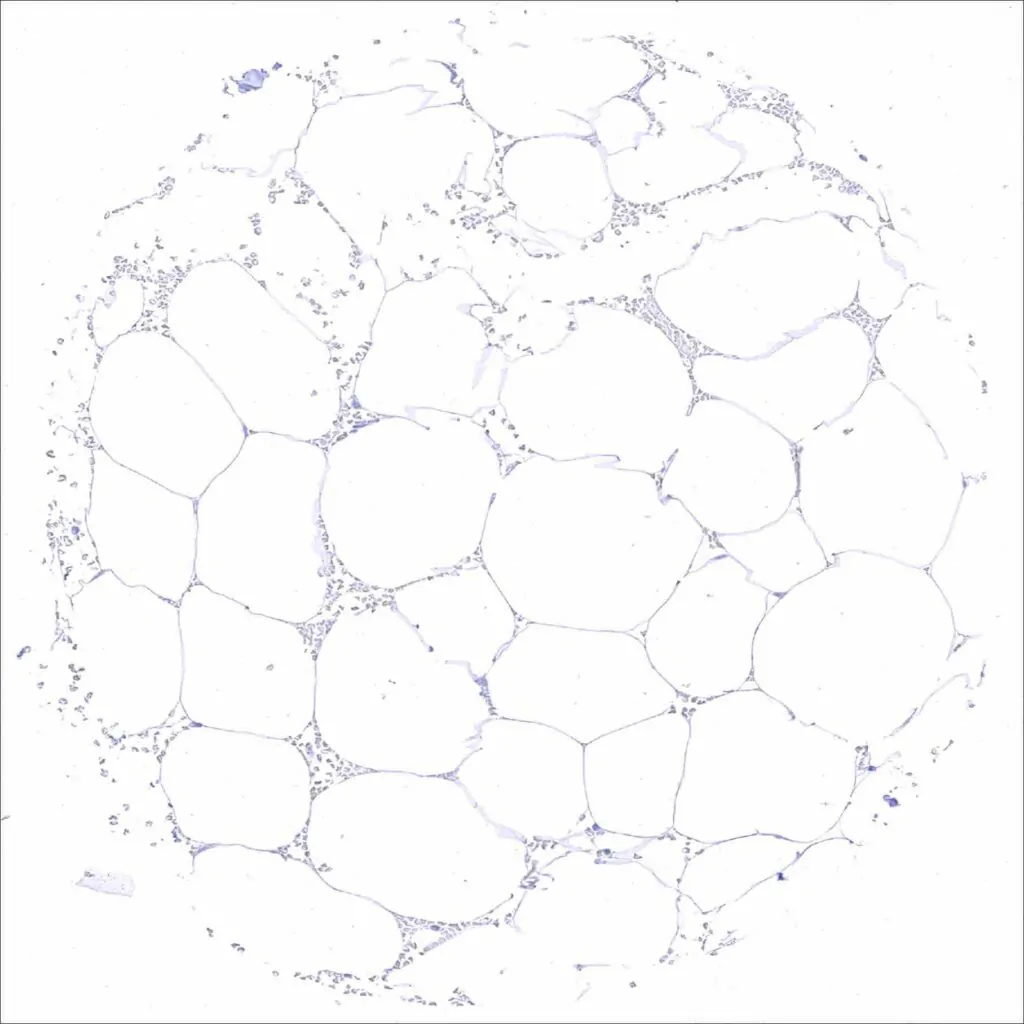

Fat